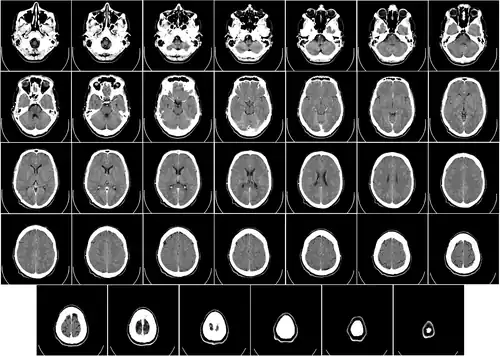

Компьютерная томография головы

Компьютерная томография (КТ) или компьютерная аксиальная томография (КАТ) использует серии рентгеновских лучей, направленных на голову, с большого количества разных направлений. Обычно её используют для быстрой визуализации ЧМТ. При КТ используют компьютерную программу, что осуществляет цифровые интегральные вычисления (инверсию преобразования Радона) измеряемой серии рентгеновских лучей. Она вычисляет, насколько эти лучи абсорбируются объёмом головного мозга. Обычно информация представлена в виде срезов мозга[4].